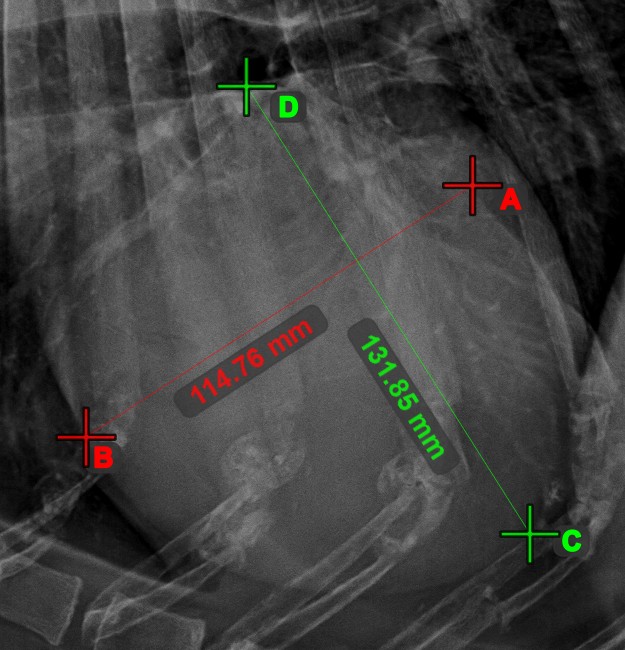

Quickly and accurately locate and mark the intersection point between two existing lines by using the Line Intersection tool.

Select the tool from the left toolbar and assign it to one of the available mouse buttons. Select two lines that have already been drawn on the scene to complete the measurement. The intersection point of the line will be automatically calculated and marked on the scene. The intersection point of two lines will always be marked with the letter X.

If two lines do not intersect directly, the intersection point of their extended projections on the scene will be marked.